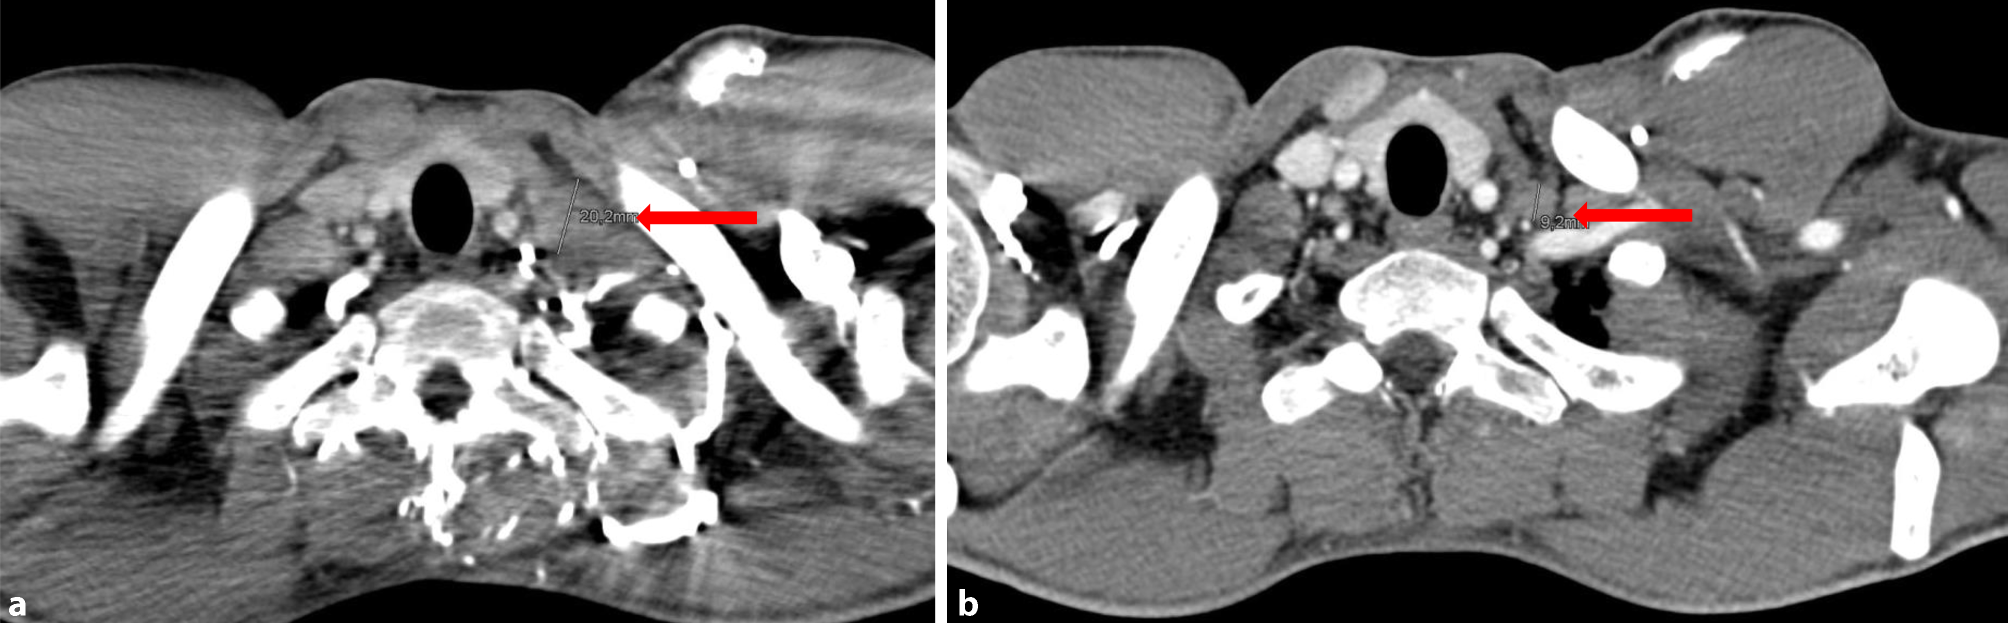

Fig. 1

Virchow’s triad: a March 2017, b June 2017

The patient received six cycles of palliative chemotherapy with docetaxel, cisplatin, 5‑fluorouracil (DCF) from June 2016 to October 2016 in a local hospital in Vienna. Although a partial response was seen after three cycles, the final CT scan exhibited progressive disease. Consequently, the hospital changed the treatment to pembrolizumab, which was given for three cycles every 3 weeks with a dose of 200 mg until January 2017. A subsequent restaging CT showed progressive disease; therefore, pembrolizumab was discontinued and no alternative treatment was given. Five months after discontinuation of the pembrolizumab treatment (June 2017), a new staging CT showed significant shrinkage of the metastases in Virchow’s triad (Fig. 1a, b), lung (Fig. 2a, b), liver (not shown), and lymph nodes (not shown). This spontaneous regression was remarkable, since the patient did not receive any treatment during this period.